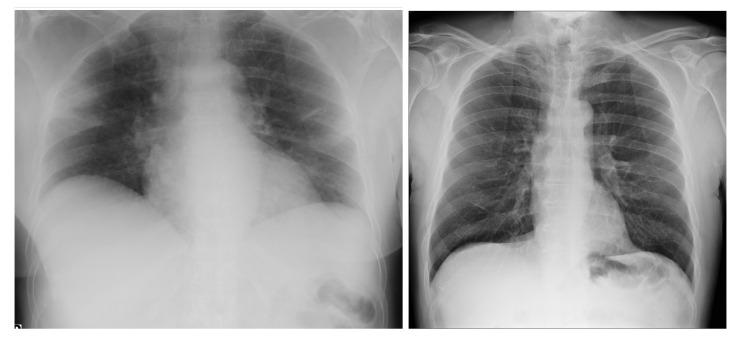

COVID-19,which is caused by the severe acute respiratory syndrome coronavirus 2 (SARS-CoV-2), is one of the worst pandemics in recent history. The identification of patients suspected to be infected with COVID-19 is becoming crucial to reduce its spread. We aimed to validate and test a deep learning model to detect COVID-19 based on chest X-rays. The recent deep convolutional neural network (CNN) RegNetX032 was adapted for detecting COVID-19 from chest X-ray (CXR) images using polymerase chain reaction (RT-PCR) as a reference. The model was customized and trained on five datasets containing more than 15,000 CXR images (including 4148COVID-19-positive cases) and then tested on 321 images (150 COVID-19-positive) from Montfort Hospital. Twenty percent of the data from the five datasets were used as validation data for hyperparameter optimization. Each CXR image was processed by the model to detect COVID-19. Multi-binary classifications were proposed, such as: COVID-19 vs. normal, COVID-19 + pneumonia vs. normal, and pneumonia vs. normal. The performance results were based on the area under the curve (AUC), sensitivity, and specificity. In addition, an explainability model was developed that demonstrated the high performance and high generalization degree of the proposed model in detecting and highlighting the signs of the disease. The fine-tuned RegNetX032 model achieved an overall accuracy score of 96.0%, with an AUC score of 99.1%. The model showed a superior sensitivity of 98.0% in detecting signs from CXR images of COVID-19 patients, and a specificity of 93.0% in detecting healthy CXR images. A second scenario compared COVID-19 + pneumonia vs. normal (healthy X-ray) patients. The model achieved an overall score of 99.1% (AUC) with a sensitivity of 96.0% and specificity of 93.0% on the Montfort dataset. For the validation set, the model achieved an average accuracy of 98.6%, an AUC score of 98.0%, a sensitivity of 98.0%, and a specificity of 96.0% for detection (COVID-19 patients vs. healthy patients). The second scenario compared COVID-19 + pneumonia vs. normal patients. The model achieved an overall score of 98.8% (AUC) with a sensitivity of 97.0% and a specificity of 96.0%. This robust deep learning model demonstrated excellent performance in detecting COVID-19 from chest X-rays. This model could be used to automate the detection of COVID-19 and improve decision making for patient triage and isolation in hospital settings. This could also be used as a complementary aid for radiologists or clinicians when differentiating to make smart decisions.

COVID-19 是由严重急性呼吸综合征冠状病毒 2(SARS-CoV-2)引起的,是最近历史上最严重的大流行之一。识别疑似感染 COVID-19 的患者对于减少其传播至关重要。我们旨在验证和测试一种基于胸部 X 光片检测 COVID-19 的深度学习模型。最近的深度卷积神经网络(CNN)RegNetX032 经过适应,可使用聚合酶链反应(RT-PCR)作为参考,从胸部 X 光(CXR)图像中检测 COVID-19。该模型在包含超过 15000 张 CXR 图像(包括 4148 例 COVID-19 阳性病例)的五个数据集上进行了定制和训练,然后在蒙福特医院的 321 张图像(150 例 COVID-19 阳性病例)上进行了测试。五个数据集的 20%的数据用于超参数优化的验证数据。模型处理每张 CXR 图像以检测 COVID-19。提出了多二进制分类,例如:COVID-19 与正常,COVID-19+肺炎与正常,肺炎与正常。性能结果基于曲线下面积(AUC)、敏感性和特异性。此外,还开发了一个可解释性模型,该模型证明了所提出的模型在检测和突出疾病迹象方面具有出色的性能和高度的泛化能力。经过微调的 RegNetX032 模型的整体准确率达到 96.0%,AUC 评分为 99.1%。该模型在检测 COVID-19 患者的 CXR 图像中的迹象方面表现出优越的敏感性,达到 98.0%,在检测健康 CXR 图像方面具有 93.0%的特异性。第二个场景比较了 COVID-19+肺炎与正常(健康 X 射线)患者。该模型在蒙福特数据集上的总体评分为 99.1%(AUC),具有 96.0%的敏感性和 93.0%的特异性。对于验证集,该模型的平均准确率为 98.6%,AUC 评分为 98.0%,敏感性为 98.0%,特异性为 96.0%用于检测(COVID-19 患者与健康患者)。第二个场景比较了 COVID-19+肺炎与正常患者。该模型的总体评分为 98.8%(AUC),敏感性为 97.0%,特异性为 96.0%。该强大的深度学习模型在从胸部 X 光片中检测 COVID-19 方面表现出出色的性能。该模型可用于自动检测 COVID-19,并提高医院环境中患者分诊和隔离的决策能力。当进行区分以做出明智决策时,它也可以作为放射科医生或临床医生的辅助工具。